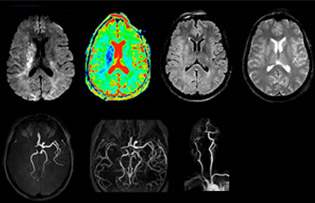

Bei der Schlaganfall-Bildgebung zählt jede Minute

„In Frankreich werden Schlaganfälle in der Regel per MRT und nicht per CT untersucht, auch bei der Notfallbehandlung.“ „In Frankreich erfolgt die Bildgebung bei Schlaganfällen in der Regel per MRT, nicht per CT, auch bei der Notfallbehandlung. Das liegt daran, dass wir mit der MRT eine Ischämie in der akuten Phase direkt darstellen, aber auch Differenzialdiagnosen wie MS und Hämatom ausschliessen können. Ausserdem ist es uns möglich, die intrakraniellen und extrakraniellen Gefässe im Laufe derselben Untersuchung zu beurteilen“, sagt Dr. Savatovsky.

Die erste Herausforderung bei der Magnetresonanztomographie betrifft die Geschwindigkeit. Die Patienten werden in der Regel aus einem Rettungswagen in den MRT-Vorbereitungsraum gebracht und die Einrichtung erfolgt an einem separaten Platz ausserhalb des Technikraums. „Der venöse Zugang wird während der neurologischen Untersuchung gelegt. Wenn es der zeitliche Abstand von den ersten Symptomen erlaubt, dass der Patient eine Thrombolyse erhält, führen wir eine sehr schnelle Untersuchung durch, die üblicherweise etwa 11 Minuten dauert, einschliesslich der Pre-Scans. Bei einem transienten ischämischen Schlaganfall erfolgt im Regelfall zusätzlich eine ASL-Perfusionsbildgebung, weil bei manchen Symptomen mit negativer Diffusion ASL eine vaskuläre Ursache anzeigt.“

„Ingenia bietet eine grosse Flexibilität bei der Parametereinstellung, d.h., wir können eine Sequenz beliebig abstimmen“, erklärt Dr. Savatovsky. „Bei einer Schlaganfalluntersuchung nutzen wir zum Beispiel eine FLAIR-Sequenz von etwa zwei Minuten anstelle der vierminütigen Sequenz, die wir bei MS verwenden. Die Diffusionsbildgebung dauert 30 Sekunden, der T2*-gewichtete Scan ebenfalls 30 Sekunden und die Scan-Dauer bei der Angiographie beträgt weniger als eine Minute. Ingenia ist in dieser Situation ein grossartiger Scanner. Auch bei diesen schnellen Sequenzen erzielen wir hochwertige Bilder mit einem guten Signal-Rausch-Verhältnis. Wenn wir anhand der ersten Sequenz feststellen, dass es sich nicht um einen ischämischen Schlaganfall, sondern um einen hämorrhagischen Schlaganfall handelt, können wir zu einer zeitaufgelösten Angiographie wechseln, um nach vaskulären Malformationen und einer Venenthrombose zu suchen.“

„Jede Klinik arbeitet anders, aber für mich umfasst das ideale Schlaganfallprotokoll die diffusionsgewichtete Bildgebung, die FLAIR- und die schnelle suszeptibilitätsgewichtete Bildgebung“, sagt Dr. Savatovsky. „Unsere schnelle suszeptibilitätsgewichtete Bildgebung dauert nur 50 Sekunden, sie ist also genauso schnell wie die T2*-gewichtete Bildgebung. Damit werden Blutungen, aber auch Koagulationen dargestellt. Wir führen zusätzlich eine 3D-MR-Angiographie durch, die Informationen über zervikale und zerebrale Gefässe liefert. Wenn die Patienten keine sofortige Behandlung benötigen oder wenn zusätzliche Informationen erforderlich sind, um über die Therapie zu entscheiden, nehmen wir ausserdem eine Perfusionsbildgebung und eine T1-gewichtete Postkontrastbildgebung vor.“